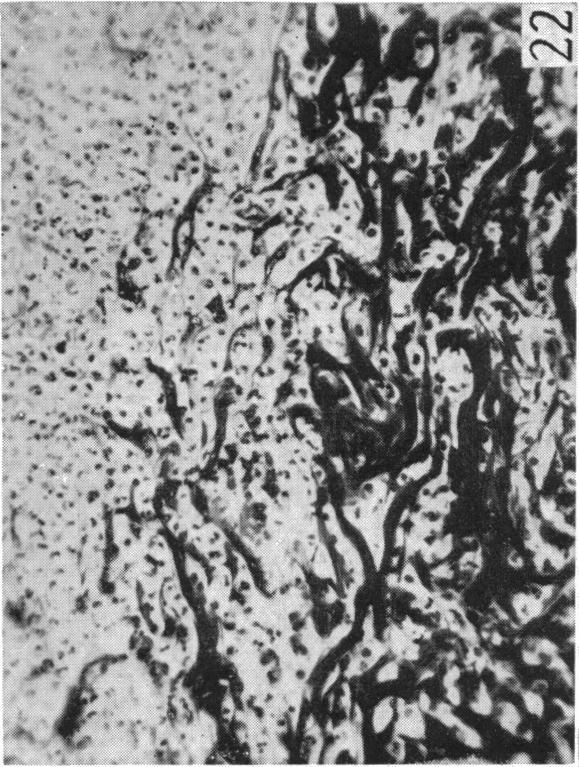

Gibson T, Medawar P B

Mr Clark's Surgical Unit, Glasgow Royal Infirmary.

J Anat. 1943 Jul;77(Pt 4):299-310.4.